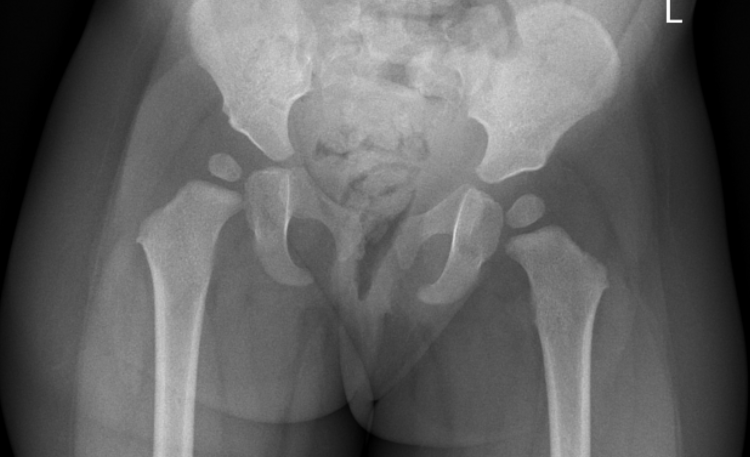

Developmental Dysplasia of the Hip (DDH): Diagnostic Imaging with Ultrasound vs. X-Ray

Learn the pros and cons of physical exam maneuvers, high risk features, and diagnostic imaging pearls for suspected developmental dysplasia of the hip (DDH).